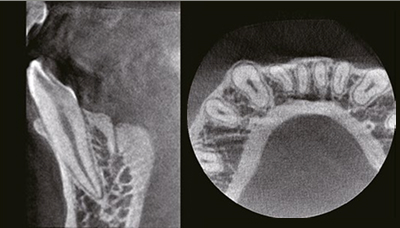

Эндодонтия

Сканирование и реконструкция при 70 мкм с фокусированным углом обзора для точных эндодонтических снимков.